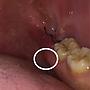

[請益] 拔水平智齒牙齦的嘴破

[ teeth_salon ]9 留言, 推噓總分: +4

作者: allgoodthing - 發表於 2019/12/14 00:30(6年前)

9Friver: 覺得那好猛,敢把嘴巴張那麼開,照相技術也好好12/14 18:59